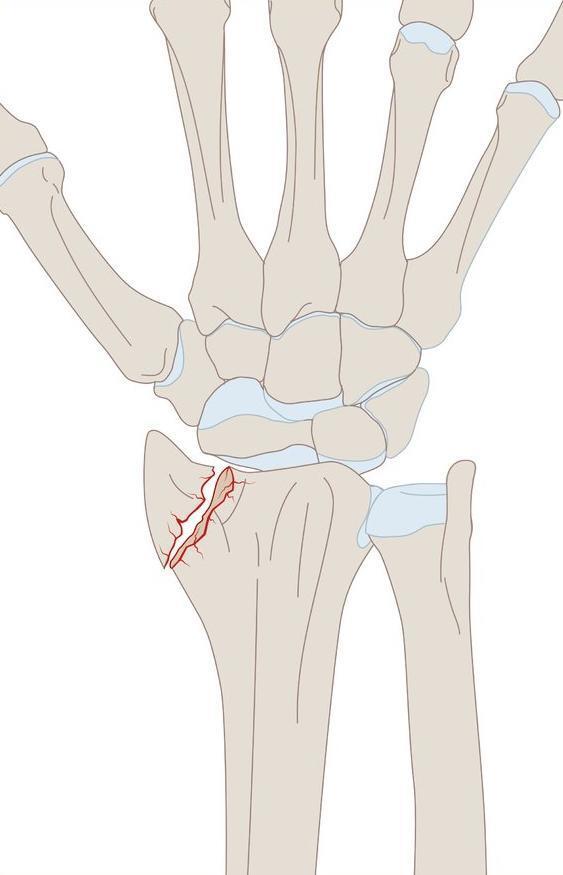

Fratura de Chauffeur

Fratura do processo estiloide do rádio. (Nao tem deslocamento)